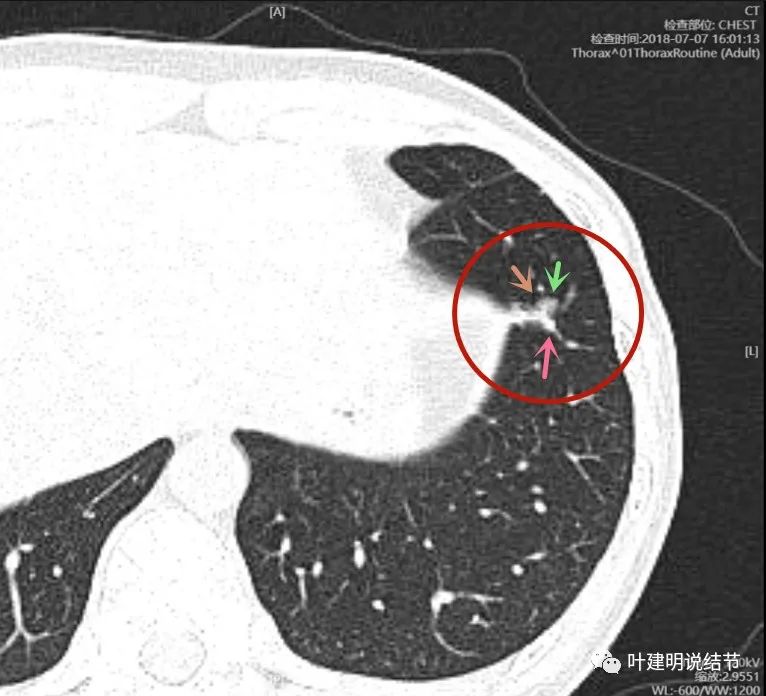

2018年7月的CT图像:

上图层面明显是混合磨玻璃病灶,轮廓清楚,有分叶(砖色箭头)、瘤肺边界清,且有显著磨玻璃成分(绿色箭头),实性成分当时就有(粉色箭头),而且密度不低。感觉与恶性很符合。